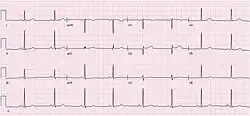

| Telemetry strip of an asymptomatic sinus pause during COVID-19 pneumonia. | |

Electrocardiogram (ECG) of a 64-year-old female with sinus bradycardia. Heart rate 49 bpm.

Electrocardiogram (ECG) of a 64-year-old female with sinus bradycardia. Heart rate 49 bpm. Electrocardiogram from a man with tachycardia-bradycardia syndrome following mitral valvuloplasty, resection of the left atrial appendage, and maze procedure. The ECG shows AV-junctional rhythm resulting in bradycardia at around 46 beats per minute.